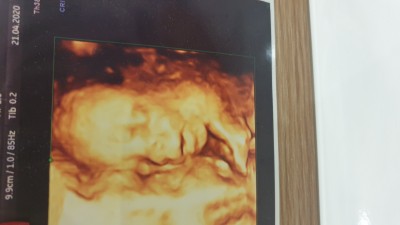

image

22 haftalikti burda detayli ultrasyondan canim